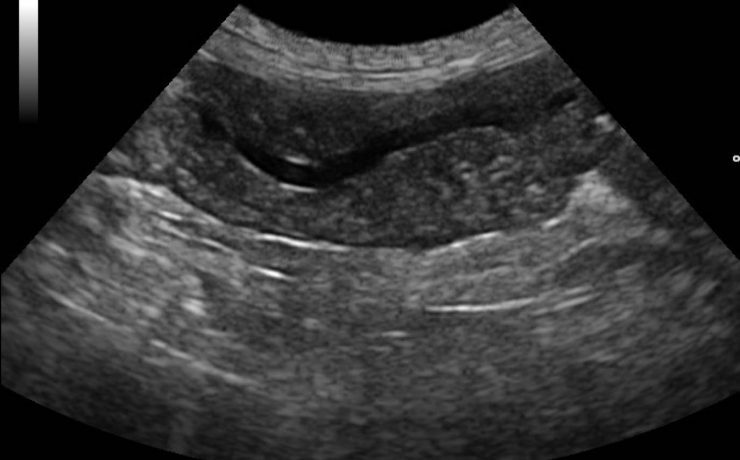

Vesícula biliar

La vesícula biliar se divide en fundus, cuerpo y cuello, en el cuello puede haber un infundíbulo o “Bolsa de Hartmann” Puede haber falta de visualización por: Colecistectomía previa Contracción fisiológica Conducto de vesícula biliar fibrosado: colecistitis crónica Vesícula biliar llena de aire o colecistitis enfisematosa Agenesia Localización ectópica PATOLOGIA